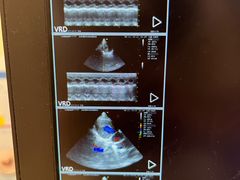

• 瑞派·关忠动物医院·异宠专科·犬猫肿瘤·皮肤专科(望京店)

• -瑞派·关忠动物医院·异宠专科·犬猫肿瘤·皮肤专科(望京店)